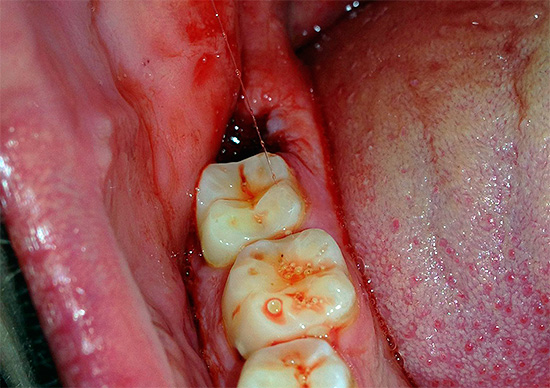

Зуб мудрости в нижней челюсти часто вызывает проблемы при прорезывании, что сопровождается воспалением десны. В таких случаях стоматологи могут рекомендовать иссечение капюшона для уменьшения травматичности. Если же рост зуба приводит к серьезным осложнениям, врачи предпочитают его полное удаление.

Процедура удаления зуба мудрости может быть травматичной для окружающих тканей, что приводит к образованию раны на слизистой, а также повреждению костей, связок и сосудов.

После удаления зуба мудрости в мягких тканях остается лунка, где находился корень. Эта рана может быть обширной, так как восьмерки — самые крупные зубы с сложной корневой системой. Увеличивается риск попадания остатков пищи и бактерий в глубокие слои тканей.

Удаление зуба мудрости может быть затруднительным. Он может расти неправильно, находиться под десной и занимать значительное пространство в мягких тканях. Восьмерки имеют сложную разветвленную корневую систему с тремя глубокими корнями. Во время удаления возможно повреждение нервных и кровеносных окончаний, связок и мышц.